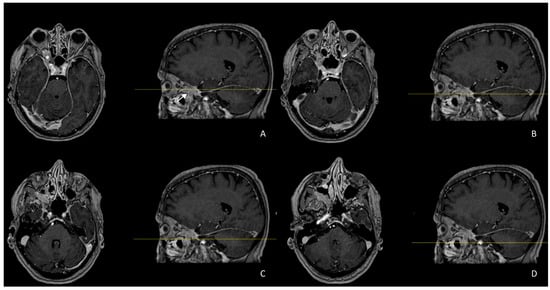

| Arrivi et al., 2023 (our case) | 77/F | Proptosis, loss of vision | PET-CT Ga-68 PET-CT 18-F, MRI, total body CT, CT Enterography Visual acuity exam | WD-NET G2 (Ki-67 6%) | WD-NET | Right Orbit | Lanreotide | OS 3 y |